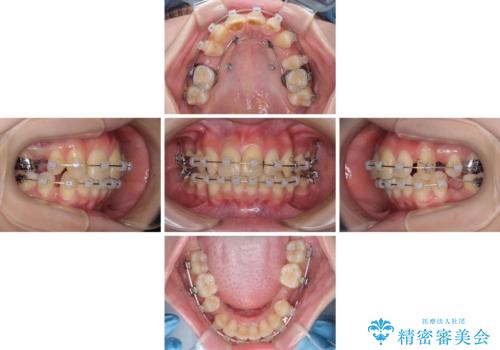

出っ歯を治したい ワイヤー装置による抜歯矯正

- 上下の出っ歯を気にして来院された患者様です。

口元を積極的に引っ込めるために、上下左右の小臼歯を4本抜歯することとしました。

右上前から2番目の歯が欠損しているため、①矯正治療により欠損部にスペースを作りインプラント補綴を行って前歯を左右対称に揃える、②左右非対称となるが、欠損補綴を行わずに排列する、のいずれかとなりますが、患者様と相談の上②にて矯正治療を行うこととしました。

変則的な歯列であったため、奥歯がしっかりと咬み合うのか、前歯はしっかりと排列できるのかと不安ではありましたが、結果としてはきれいに整った歯列にて終了することができました。